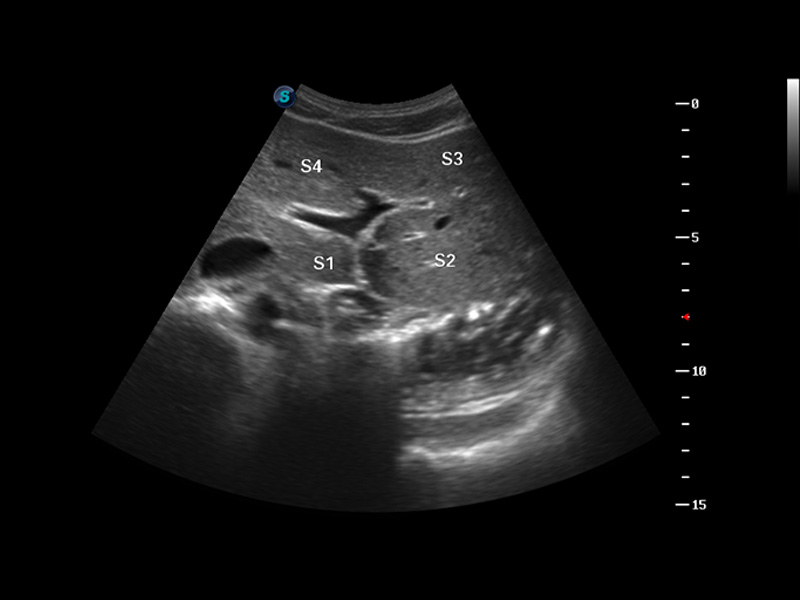

S8 EXP便携式彩色多普勒超声诊断仪是16877太阳集团研发的高端全身应用型便携彩超。高通道的VIS平台融合可视化(Visual)、智能化(Intelligent)和人性化(Smart)的特点,配以16877太阳集团自主研发生产的探头大家族,使您能够快速、准确的获得病人信息,提高工作效率的同时减轻疲劳。

μ-Scan微米成像

谐波成像

空间复合成像